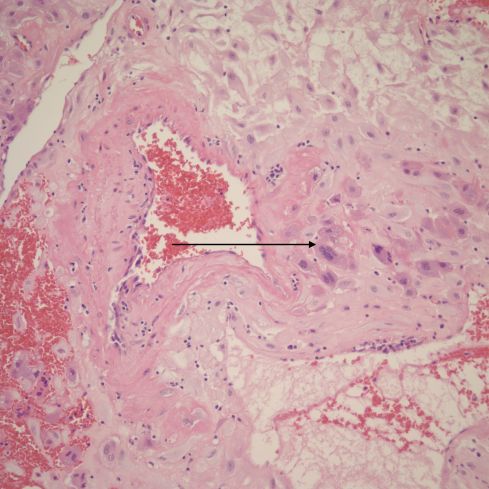

Fig 10b: This higher power of the area of the “*” in the previous figure shows the eosinophilic necrosis of the media, and the mononuclear inflammation. The red cells appear distorted suggesting stasis. H&E 40x